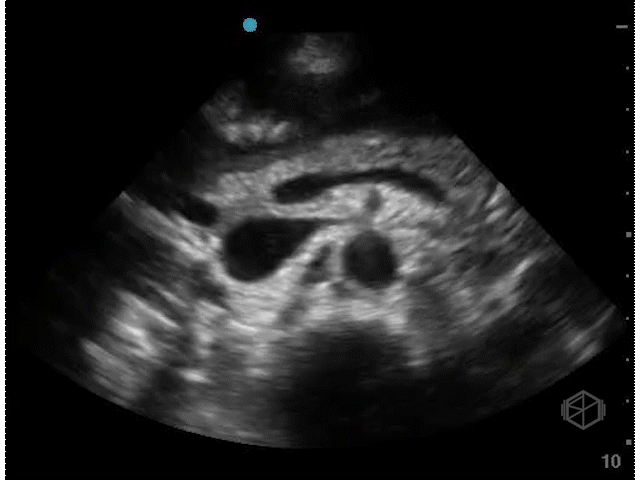

The first SonoProps goes to our current resident rotator Dr. Antonia Nevias-Ida.

She was scanning a 55-year-old female with LEFT flank pain that came on sudden onset and captured the following images:

If you are thinking this is positive for free fluid — surprise — it is not!

It is actually an artifact called lipliner sign. Free fluid generally makes sharp angles and persists throughout multiple views, where as this anechoic stripe disappears as the probe position is varied.

Diagnosis: Lipliner sign

• There are many misleading artifacts and false positives to consider when performing a FAST/FAFF examination including focal fatty sparing, double line sign, and now the lipliner sign.

• Lipliner sign is an artifact that appears at the edge of solid organs such as the liver or the spleen (the more common areas for free fluid) (39366788) and can easily mislead a clinician to assume there is free fluid present.

• It is not definitively known what causes the lipliner sign but it may be due to advances in ultrasound machines likely due to adaptive filtering to improve spatial resolution and post-processing technology.

• The artifact may be visible on machines from multiple manufacturers.

• When encountering lipliner artifact and deciding it may be reasonable to call the FAST equivocal rather than a true positive if there is any question.

• True free fluid makes sharp angles, dissects through structures, is dependent, should not have any membranes or walls, and is dynamic (eg, place the patient in Trendelenburg and more fluid will shift up).